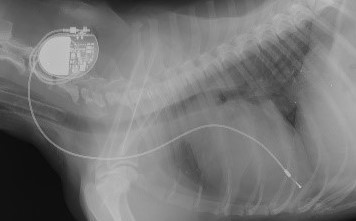

不整脈診断・心臓ペースメーカー治療

不整脈の診断・心臓ペースメーカー治療を行います。

心内膜法、心外膜法、ヂュアルチェンバー法などを行っています。

3)ペースメーカー埋込術

4)長期生活指導及び設定調整

ペースメーカー療法

カテーテル法

|

低侵襲

離脱可能性

開胸法

安定性(離脱可能性低)

入院治療が必要(3-5日)

犬・ネコの場合は全身の柔軟性や可動域が広いためにリード線が安定固着後でも離脱することがあります。

そのため開胸法をお勧めしていますがどちらも可能です。